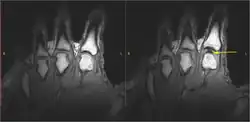

In 2015, research showed that bubbles remained in the fluid after cracking, suggesting that the cracking sound was produced when the bubble within the joint was formed, not when it collapsed.[8] In 2018, a team in France created a mathematical simulation of what happens in a joint just before it cracks. The team concluded that the sound is caused by bubbles' collapse, and bubbles observed in the fluid are the result of a partial collapse. Due to the theoretical basis and lack of physical experimentation, the scientific community is still not fully convinced of this conclusion.[2][13][14]